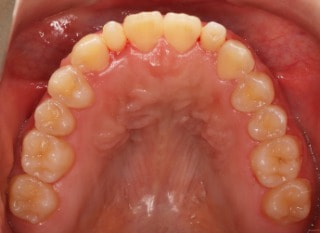

治療前